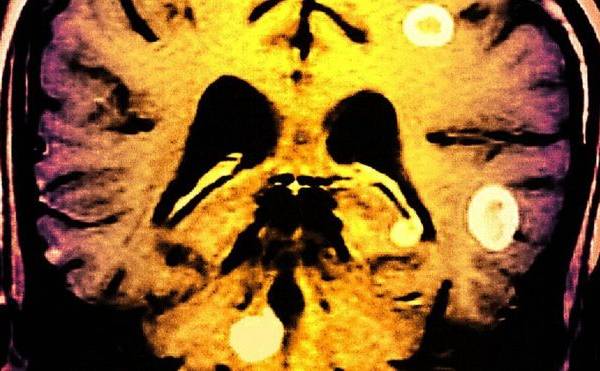

Tuberculosis en el cerebro: "El dolor es tan fuerte que me dan ganas de cortarme la cabeza"

Aunque sufrir de tuberculosis en el cerebro es inusual, la enfermedad es común.

Johnny Islam, 29, es de Leyton, un barrio de Londres. Aunque sufrir de tuberculosis en el cerebro es inusual, la enfermedad en sí es más común de lo que se piensa.

La enfermedad le cambió la vida a Johnny. Podría causarle daño permanente y hasta matarlo.

"Se puede propagar a todas las células cerebrales, puede perjudicar tu memoria. A mí se me olvidan cosas todo el tiempo".

"La tuberculosis podría matarme... cualquier cosa puede pasar", le dice Johnny a la BBC, aunque agrega que "todos nos vamos a morir un día".

Se trata de una infección bacteriana que ataca principalmente los pulmones, pero puede afectar cualquier parte del cuerpo.